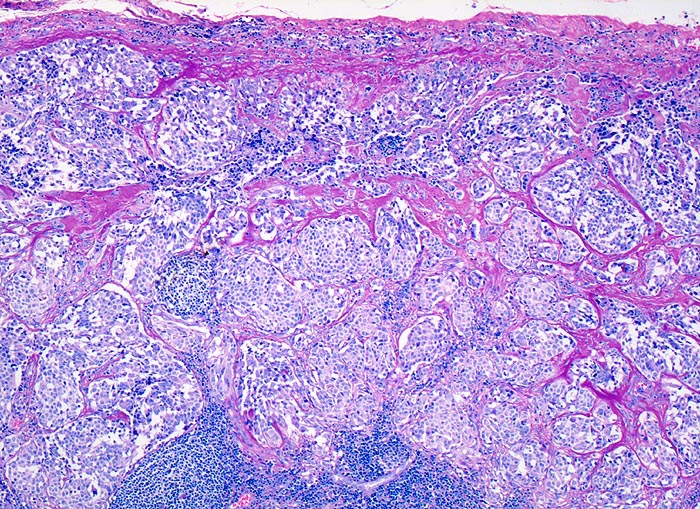

PathoPic – image database / PathoPic ID 3744 - medulläres Schilddrüsenkarzinom: Lymphknotenmetastase

medulläres Schilddrüsenkarzinom: Lymphknotenmetastase

Lymphknoten, Kopf-cervikal

Spärlicher Reste von lymphatischem Gewebe unten im Bild. Tumorinfiltrat aus soliden monomorphen Zellballen umgeben von breiten Sklerosesepten.

Calcitonin in den Tumorzellen positiv.

Verschiedene Tumormetastasen können ein malignes Lymphom vortäuschen: Nasopharynxkarzinom, malignes Melanom, Seminom, Merkelzellkarzinom. Andererseits können maligne Lymphome Karzinom- oder Melanommetastasen imitieren: grosszellig anaplastische Lymphome.